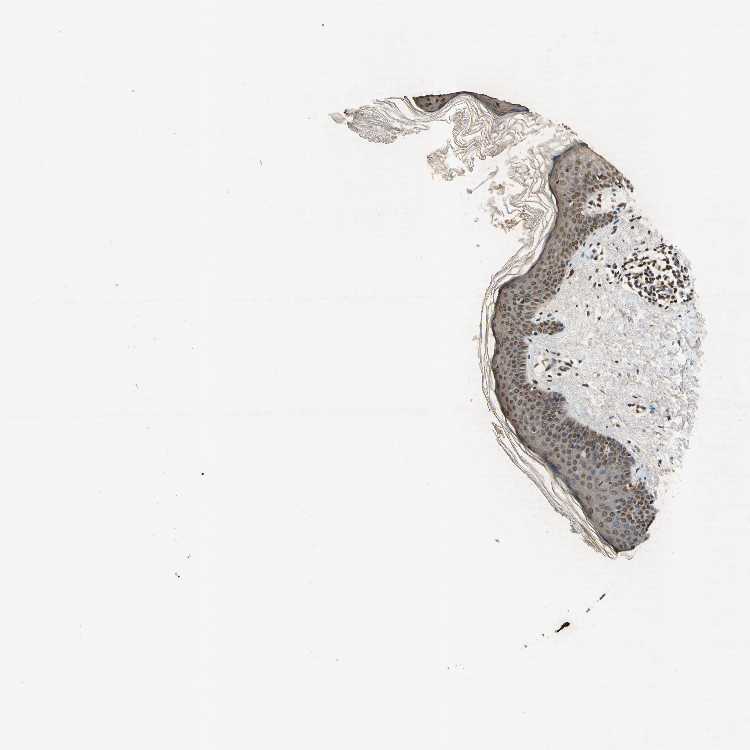

SKIN 1 - Antibody stainingi

Antibody staining in the annotated cell types in the current human tissue is reported as not detected, low, medium, or high, based on conventional immunohistochemistry profiling in selected tissues. This score is based on the combination of the staining intensity and fraction of stained cells.

Each image is clickable and will lead to virtual microscopy that enables deeper exploration of all samples and also displays staining intensity scores, fraction scores and subcellular localization as well as patient and tissue information for each sample.

Antibody CAB009860

Langerhans High

Fibroblasts Medium

Keratinocytes Medium

Melanocytes Low